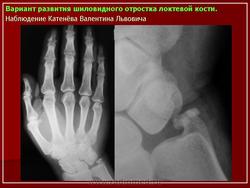

"Дублирование" фаланг